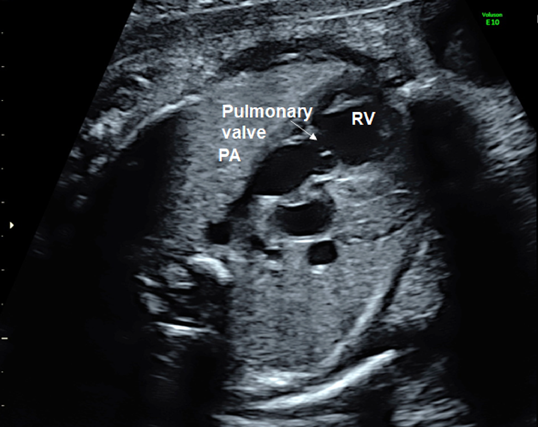

(4) Observation of Outflow Tracts

Tilting the probe toward the head of the fetus during the 4CV gives a view of the ventricular outflow tracts (Fig. 7). The left ventricular outflow tract (the aorta does not branch immediately after originating from the ventricle) is visualized first (Fig. 10), then the right ventricular outflow tract (the pulmonary artery branches immediately after originating from the ventricle) with further tilting (Fig. 11). The whole picture of the major vessels and their connections to the ventricles can be seen in the long-axis view. The normal features of the outflow tracts are; 1) a couple of major vessels present with the pulmonary arterial trunk greater than the aorta, 2) these vessels crossing each other spatially, 3) the vessels arising one each from the ventricles, and 4) the interventricular septum and the anterior wall of the aorta being a continuum.

(3) Observation of the Outflow Tracts

The left ventricular outflow tract can be visualized by tilting the probe cranially from the 4CV position. Further tilting demonstrates the right ventricular outflow tract. These outflow tracts typically form a crossover spiral, with the left ventricular outflow tract going from left to right, and the right going from right to left. Further tilting of the probe reveals the bifurcation of the left and the right pulmonary arteries. This view confirms the pulmonary arterial trunk and the aorta originate from the right and the left ventricles, respectively. Abnormal positions and relationship of these structures would imply transposition of the great arteries or double outlet right ventricle. The outflow tracts in these diseases may better be understood by rotating the probe.